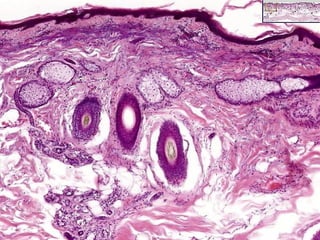

• #10 Appendages: hair follicles, sebaceous glands, sweat glands (eccrine, apocrine). Is this thick skin or thin skin?

• #41 Epidermal inclusion cyst